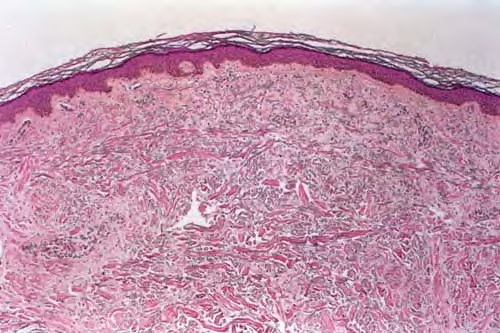

Myxoedema =الوذمة المخاطية